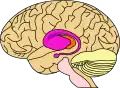

rose = noyau caudé et putamen, orange = thalamus

Le noyau caudé d'origine télencéphalique est l'un des quatre principaux composants des ganglions de la base, les trois autres étant le putamen et le globus pallidus formant tous deux le noyau lenticulaire, et la substance noire. Le striatum est l'ensemble formé par le noyau caudé et le putamen, et représente plutôt une unité fonctionnelle qu'anatomique. Ils sont en effet tous les deux la voie d'entrée dans les ganglions de la base pour les informations venant du cortex.

Le noyau caudé présente une extrémité antérieure renflée (la tête), un corps effilé et de volume décroissant et une queue.

Il s'enroule d'avant en arrière autour du thalamus où il forme la paroi latérale des ventricules latéraux, s'incurve au niveau du pulvinar, sous le splenium du corps calleux, et se réfléchit d'arrière en avant au sein du lobe temporal, au-dessus de la corne temporale du ventricule latéral, pour se terminer en arrière de l'amygdale cérébrale.